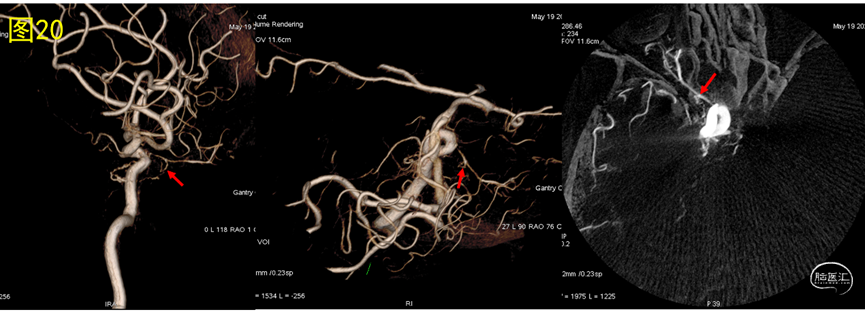

2. 再回头看,是否还有需要改进的步骤吗?图19为术后DSA-CT像,确实眼动脉走形区确实有ONYX胶弥散,一般眼动脉发出的筛动脉与脑膜中动脉前支有吻合,距离此病例的瘘口较远,一般不会。旋转右侧颈内动脉3D像发现眼动脉根部有分支动脉参与瘘口供血,这是术前未发现的(图19和图20红箭头)。